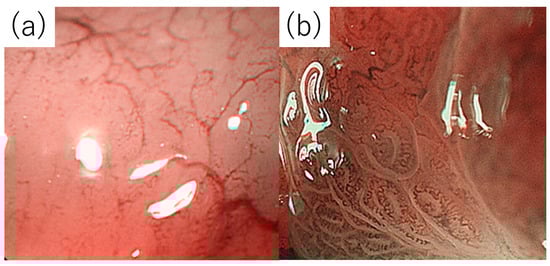

- Nonaka, K.; Ishikawa, K.; Shimizu, M.; Sakurai, T.; Nakai, Y.; Nakao, M.; Yoshino, K.; Arai, S.; Kita, H. Education and imaging. Gastrointestinal: Gastric mucosa-associated lymphoma presented with unique vascular features on magnified endoscopy combined with narrow-band imaging. J. Gastroenterol. Hepatol. 2009, 24, 1697. [Google Scholar] [CrossRef]

- Ono, S.; Kato, M.; Ono, Y.; Itoh, T.; Kubota, K.; Nakagawa, M.; Shimizu, Y.; Asaka, M. Characteristics of magnified endoscopic images of gastric extranodal marginal zone B-cell lymphoma of the mucosa-associated lymphoid tissue, including changes after treatment. Gastrointest. Endosc. 2008, 68, 624–631. [Google Scholar] [CrossRef]

- Ono, S.; Kato, M.; Ono, Y.; Nakagawa, M.; Shimizu, Y.; Asaka, M. Magnified endoscopic images of gastric MALT lymphoma before and after treatment. Endoscopy 2007, 39, E328. [Google Scholar] [CrossRef]

- Isomoto, H.; Shikuwa, S.; Yamaguchi, N.; Miyazato, K.; Ohnita, K.; Hayashi, T.; Mizuta, Y.; Ito, M.; Kohno, S. Magnified endoscopic findings of gastric low-grade mucosa-associated lymphoid tissue lymphoma. Endoscopy 2008, 40, 225–228. [Google Scholar] [CrossRef]

- Nonaka, K.; Ishikawa, K.; Arai, S.; Nakao, M.; Shimizu, M.; Sakurai, T.; Nagata, K.; Nishimura, M.; Togawa, O.; Ochiai, Y.; et al. A case of gastric mucosa-associated lymphoid tissue lymphoma in which magnified endoscopy with narrow band imaging was useful in the diagnosis. World J. Gastrointest. Endosc. 2012, 4, 151–156. [Google Scholar] [CrossRef]

- Nonaka, K.; Ohata, K.; Matsuhashi, N.; Shimizu, M.; Arai, S.; Hiejima, Y.; Kita, H. Is narrow-band imaging useful for histological evaluation of gastric mucosa-associated lymphoid tissue lymphoma after treatment. Dig. Endosc. 2014, 26, 358–364. [Google Scholar] [CrossRef] [PubMed]